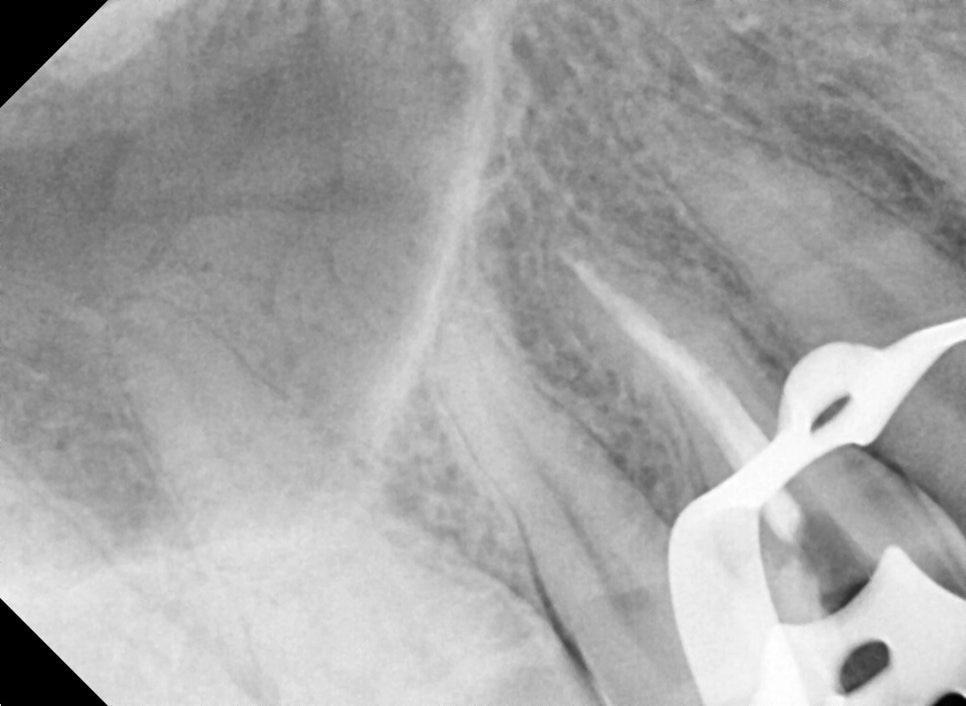

Left photo: X-ray taken during root canal treatment. This is a process to check whether the medication has reached deep inside the root canal.

Right photo: A molar being prepared for crown treatment. After the root canal treatment, the removed tooth structure has been neatly cleaned up and shaped before taking an impression.